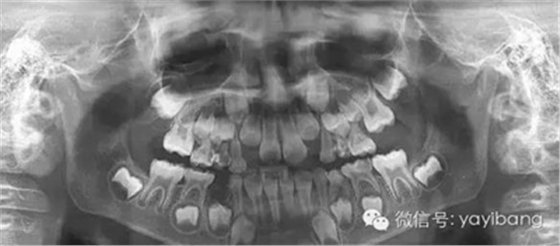

1、 患者 男 7歲 右下乳IV因齲早失

3、曲面斷層片 示恒牙萌出間隙不足